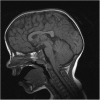

Chiari I malformation, delayed gross motor skills, severe speech delay, and epileptiform discharges in a child with FOXP1 haploinsufficiency

Human FOXP2 deficiency has been identified as a cause of hereditary developmental verbal dyspraxia. Another member of the same gene family, FOXP1, has expression patterns that overlap with FOXP2 in some areas of the brain, and FOXP1 and FOXP2 have the ability to form heterodimers. These findings suggest the possibility that FOXP1 may also contribute to proper speech development. However, no such role of FOXP1 has been established to date. Recently, a child was reported who presented with a 3p13-14.1 deletion of four genes, including FOXP1, and a constellation of deficits that included speech delay. In this study, we report the case of a patient with a single deletion of FOXP1. This patient presented with speech and motor developmental delays, a Chiari I malformation, and epileptiform discharges. The nature of the speech deficit is different from the primary oromotor verbal dyspraxia found in patients with FOXP2 deficiency. The patient's developmental deficits may support a role for FOXP1 in the development of verbal and motor skills.